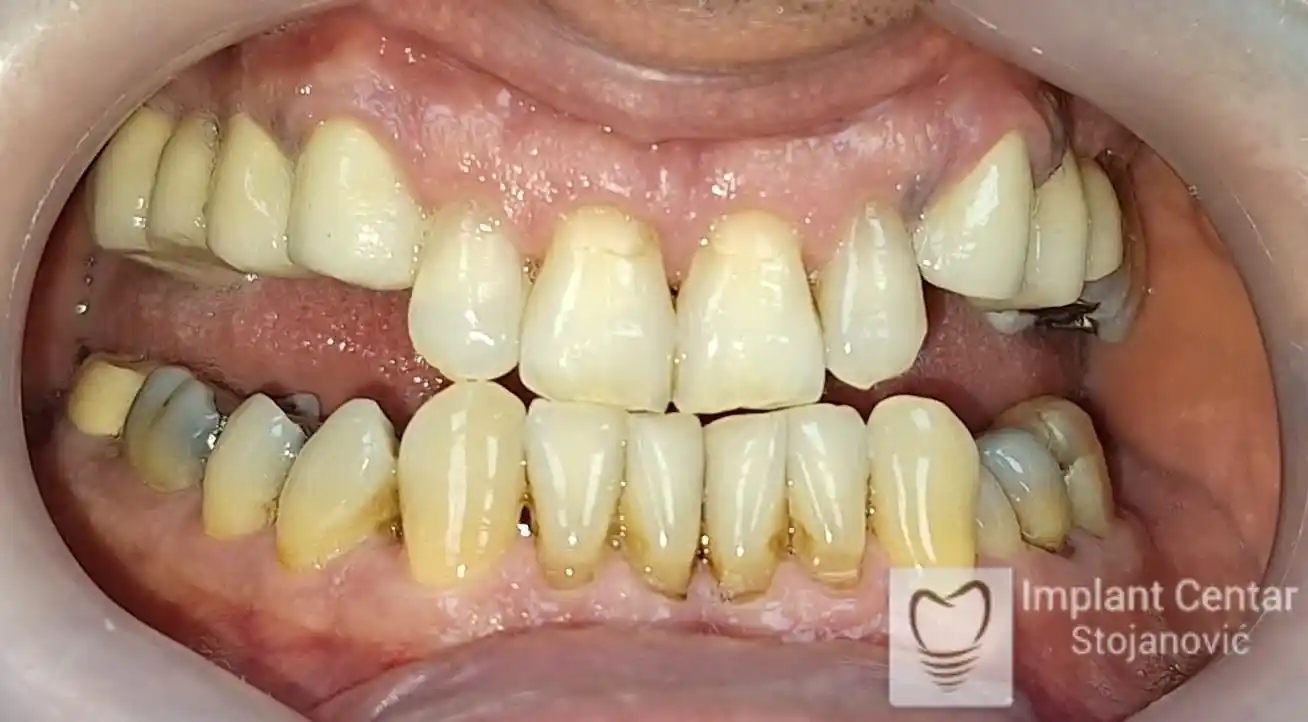

Pacijent sa rascepom usne, nepca i alveolarnog grebena uspešno je rehabilitovan fiksnim protetskim radom na implantatima. Pre dolaska u našu ordinaciju, pacijent je u gornjoj vilici nosio totalnu protezu preko preostalih zuba, dok je u donjoj vilici bio zbrinut parcijalnom mobilnom protezom. Tokom višegodišnje potrage za adekvatnim rešenjem, pacijent nije uspeo da pronađe zadovoljavajuću terapijsku opciju ni u zemlji ni u inostranstvu.

Nakon detaljnog kliničkog pregleda i analize radioloških snimaka, izrađen je sveobuhvatan plan terapije sa ciljem uklanjanja mobilnih proteza i postizanja maksimalne funkcionalne i estetske rehabilitacije. Zbog loše biološke vrednosti preostalih zuba, doneta je odluka o njihovom vađenju i ugradnji dentalnih implantata.

Na slikama 1, 2, 3 , 4  i  5 prikazan je izgled pacijenta pre početka terapije. Nakon detaljne kliničke i radiološke analize, doneta je odluka o vađenju zuba loše biološke vrednosti, dok su bezuba polja sanirana ugradnjom dentalnih implantata.